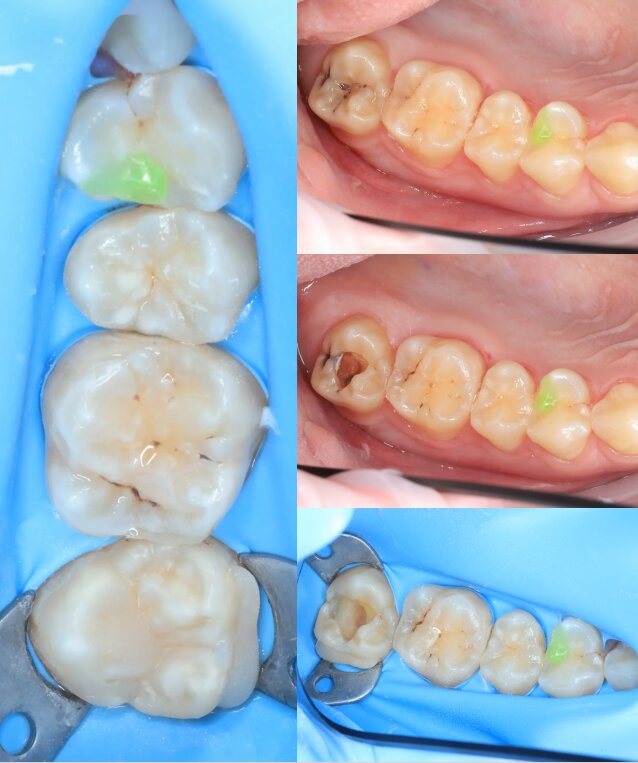

Портфоліо лікаря

У портфоліо представлені реальні клінічні випадки з практики лікаря — від первинного стану до результату лікування. Кожен кейс демонструє індивідуальний підхід, сучасні методи лікування та увагу до деталей